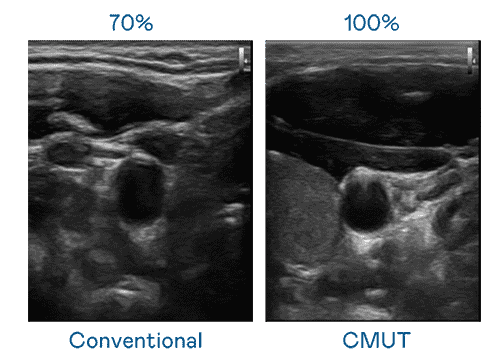

CMUT 技术是一种用电容式微机电元件来产生超音波讯号的技术。。。。与传统 PZT 压电式技术相比,,,CMUT 频宽增加 30%,,,更宽频的超音波讯号让影像解析度大幅提升,,是实现高影像品质医疗超音波扫描、、促进精准医疗发展的关键技术。。。

大频宽带来超清晰影像

超音波影像的解析度高低,,首先取决于探头能发出的讯号频宽。。z6mg·人生就是博 CMUT 可提供高清晰的超音波讯号,,,,提供高频宽、、、高灵敏度、、、影像纹理细节更高的超音波影像,,协助医护人员缩短影像判读时间及利用精准的医疗影像进行诊断。。。。